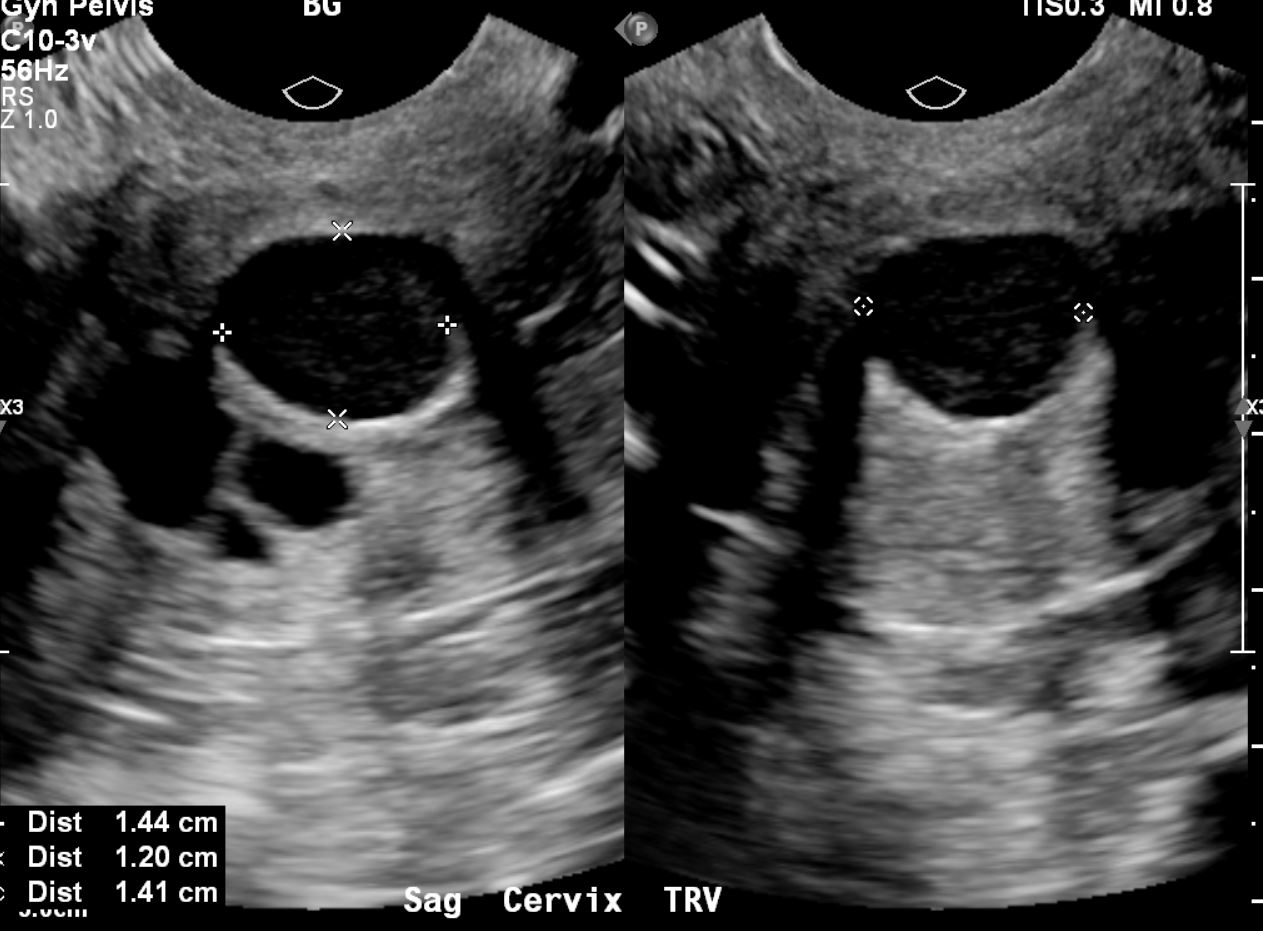

nabothian cyst in cervix II Dr Nasrin Fatema II Realtime Ultrasound II nabothian cyst in TVS

Mulher com 44 anos de idade com quistos de Naboth. a) No plano sagital… Download Scientific